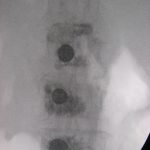

Σε ειδικές περιπτώσεις απαιτείται να γίνει και εσωτερική σταθεροποίηση της περιοχής του κατάγματος με σύστημα κοχλιών και ράβδων (εικόνα 4 α,β)

Εικόνα 4 α,β : προεγχειρητική πλαγία και προσθιοπισθία ακτινογραφία της Θ.-ΟΜ.Σ.Σ του Ε.Μ. 86 χρονών. Παρατηρείται η ύπαρξη πολλών σπονδυλικών καταγμάτων συνεπεία οτεοπόρωσης.